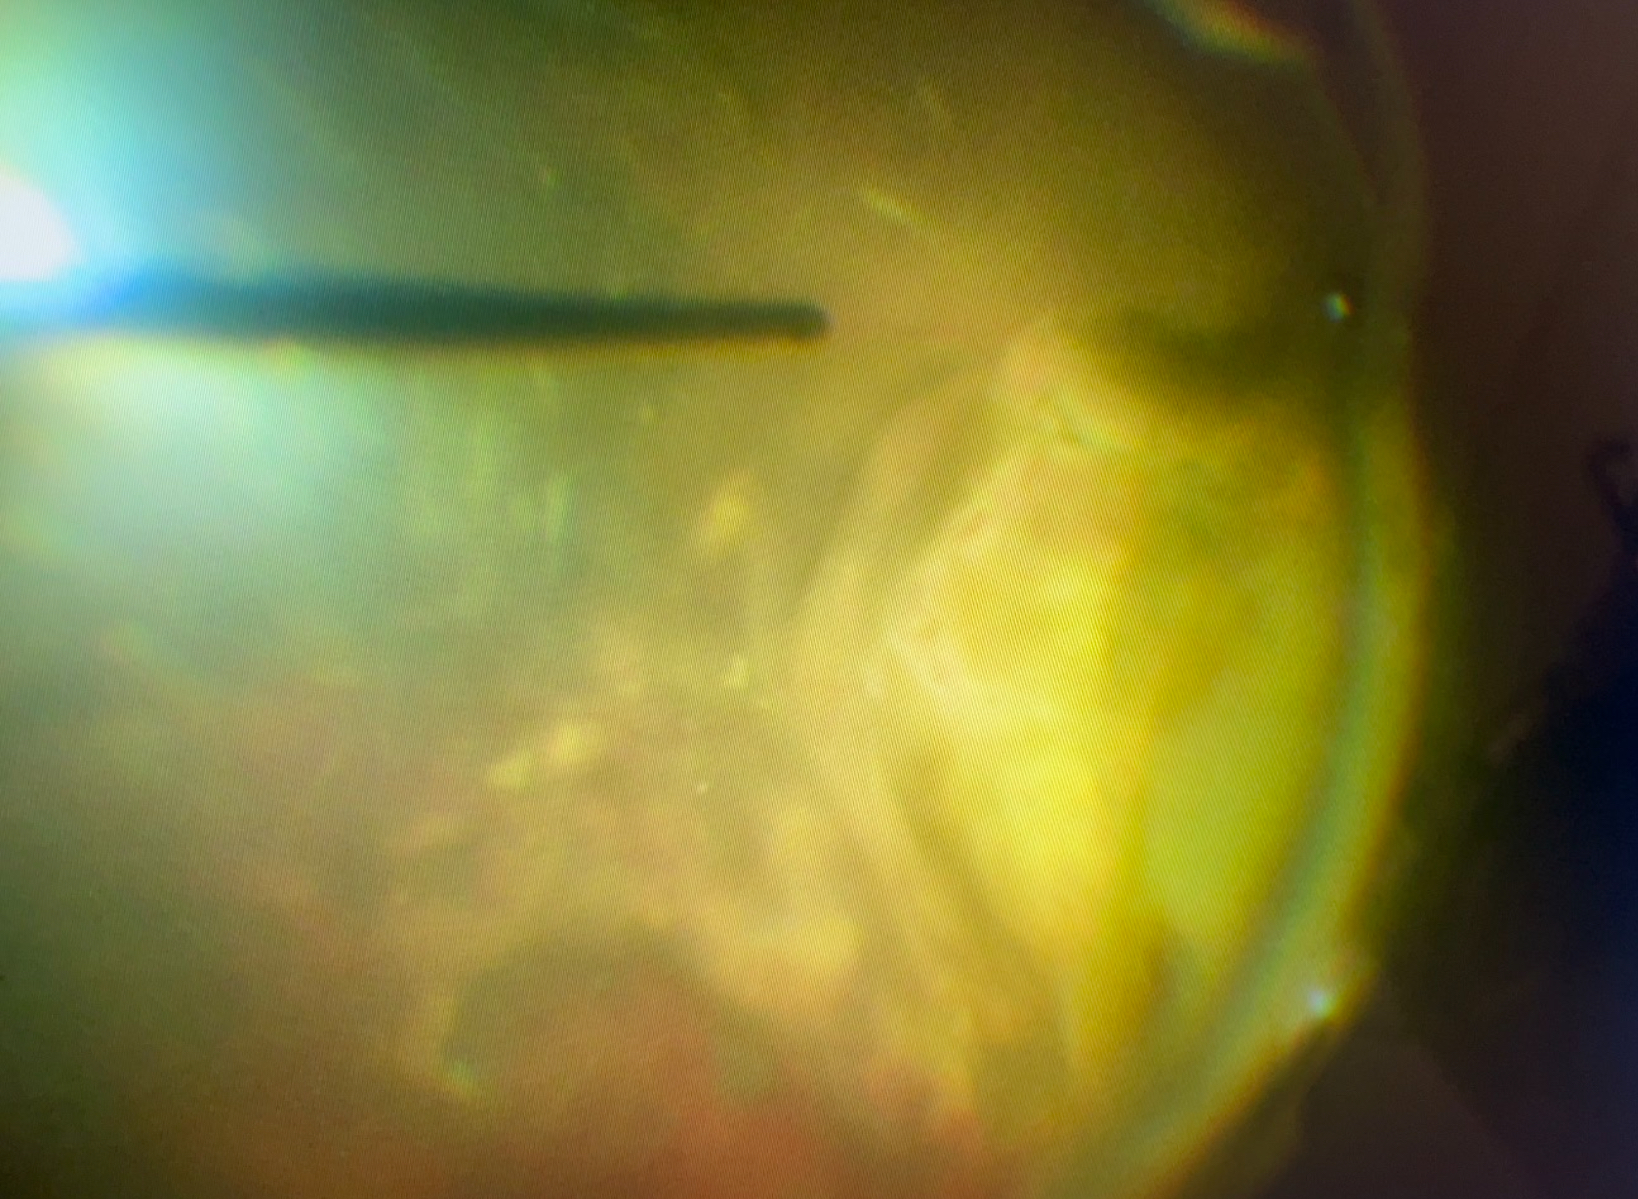

手術では、大量の硝子体出血を取り除くと、広い範囲の眼底出血が見られました。眼底出血も網膜表面の出血だけでなく、網膜自体が隆起しており、網膜の下やその更に下の脈絡膜からの出血の存在が疑われました。硝子体手術では、眼の壁の周りを外から押しながら硝子体を切除する操作を行うのですが、その時に網膜が大きく盛り上がっている部分に裂け目ができ、そこから茶色い古い出血の塊が出てくるようになりました。通常、単なる網膜の裂け目ができた場合は、レーザーで周りを固めるのですが、出血があると、レーザーの効果が得られないので、今回は眼の中にガスを入れるところまで行い、手術を終えました。